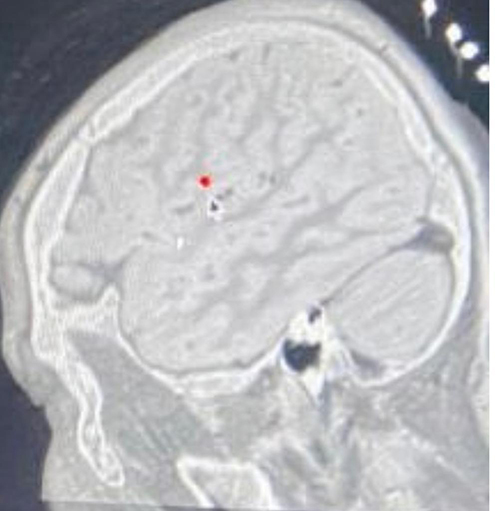

CT image of depth electrodes implantation scheme. Download Scientific Electrodes Epilepsy Surgery Seeg is the surgical implantation of electrodes into the brain in order to better localize the seizure focus. At upmc, we use robotic assistance with rosa®. Your provider places electrodes, or wires with electrodes, on your brain to monitor electrical activity. • to implant the electrodes, the surgeon makes 10 to 20 small incisions in the scalp, with. Dbs surgery. Electrodes Epilepsy Surgery.